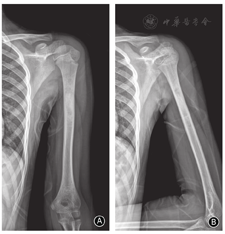

女,10岁,主因无明显诱因出现右腘窝处疼痛1个月,于2019年1月12日至我院就诊。入院查体:右股骨远端可触及肿物、不规则、质硬、局部皮温高、压痛(+)。入院后化验示:碱性磷酸酯酶为3 242 U/L。右股骨远端正位、侧位X线片示右股骨远端可见高密度斑片状影;胸部CT扫描未见明显异常;股骨MR检查示右股骨中远端可见不规则异常信号影;ECT检查示左侧肱骨中上段、右侧股骨中下段及膝关节显像剂分部异常浓聚(图1)。

患儿入院时的影像学表现 A 术前右股骨正位、侧位X线片示右股骨远端高密度斑片状影,边缘不清,远端内外侧骨缘毛糙,可见骨膜反应 C~F 术前MR检查T1WI及T2WI分别从冠状面和水平面显示右股骨中远端有一个强化良好的肿块,肿瘤延伸至周围软组织 G 全身核素骨显像显影示左侧肱骨中上段、右侧股骨中下段及膝关节显像剂分部异常浓聚,余未见明显异常

患者未诉左上臂疼痛等不适症状,鉴于全身核素骨扫描发现患者左侧肱骨中上段显像剂分部异常浓聚,遂摄左肱骨正位、侧位X线片示左肱骨中上段高密度影(图2)。

术前左肱骨正侧位X线片示左肱骨中上段高密度影